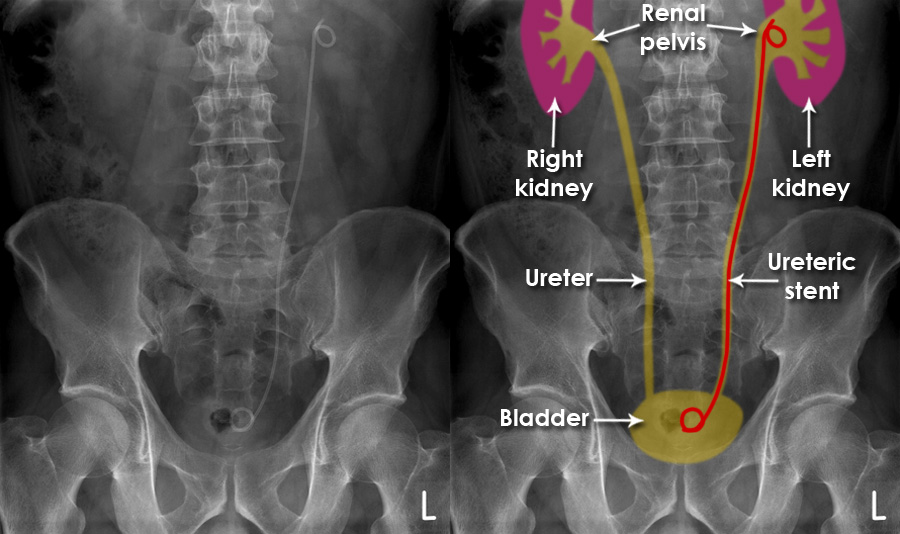

Ureteric Stent Going home Milton Keynes University Hospital new arrivals, Ureteral Stent Placement Memorial Sloan Kettering Cancer Center new arrivals, Ureteric Stent Patient Information Brochures Mater Group new arrivals, Ureteric stenting CIRSE new arrivals, Ureteroscopy and ureteric stenting for ureteric stones Urology new arrivals, Ureteric stent Macmillan Cancer Support new arrivals, IJMS Free Full Text Functional Properties of Polyurethane new arrivals, Ureteric Stent Insertion VIRQ new arrivals, Ureteric stent insertion Chelsea and Westminster Hospital NHS new arrivals, Consent Retrograde Ureteric Stent Insertion TeachMeSurgery new arrivals, Having a Ureteral Stent Saint Luke s Health System new arrivals, Ureteral Stents new arrivals, Dr Tim Nathan Urology Insertion and Removal of Ureteric Stents new arrivals, Ureteral stents are flexible tube like devices with holes new arrivals, Ureteral Stent for Parents Nemours KidsHealth new arrivals, Ureteral Stent Placement What is a ureteral stent Urology Austin new arrivals, Ureteral Stents What you need to know new arrivals, What Is Ureteral Stenting Procedure and Recovery new arrivals, Use of cystourethroscopy to remove an indwelling double J ureteral new arrivals, Ureteral Stent My Kidney Stone Boston Scientific new arrivals, Enhance Comfort and Recovery with Ureteric Stents new arrivals, Ureteral Stent Keystone Urology Specialists new arrivals, Abdominal X ray Artifacts Renal and ureteric stents new arrivals, What to Expect from a Ureteral Stent Advanced Urology new arrivals, Ureteric Stents new arrivals, Your Guide to Ureteral Stents For Kidney Stones Worst Pain Ever new arrivals, Cystoscopy and Ureteral Stent Placement new arrivals, Determination of urinary prostaglandin E2 as a potential biomarker new arrivals, Nephrostomy and ureteric stenting CIRSE new arrivals, Outcomes of outpatient ureteral stenting without fluoroscopy at new arrivals, Ureteral Stents Boston Scientific new arrivals, Ureteral Stent Placement new arrivals, Surface engineered biomaterials and ureteral stents inhibiting new arrivals, Ureteric Stent Insertion OneWelbeck Men s Health new arrivals, Calcified ureteric stent Radiology Case Radiopaedia new arrivals.